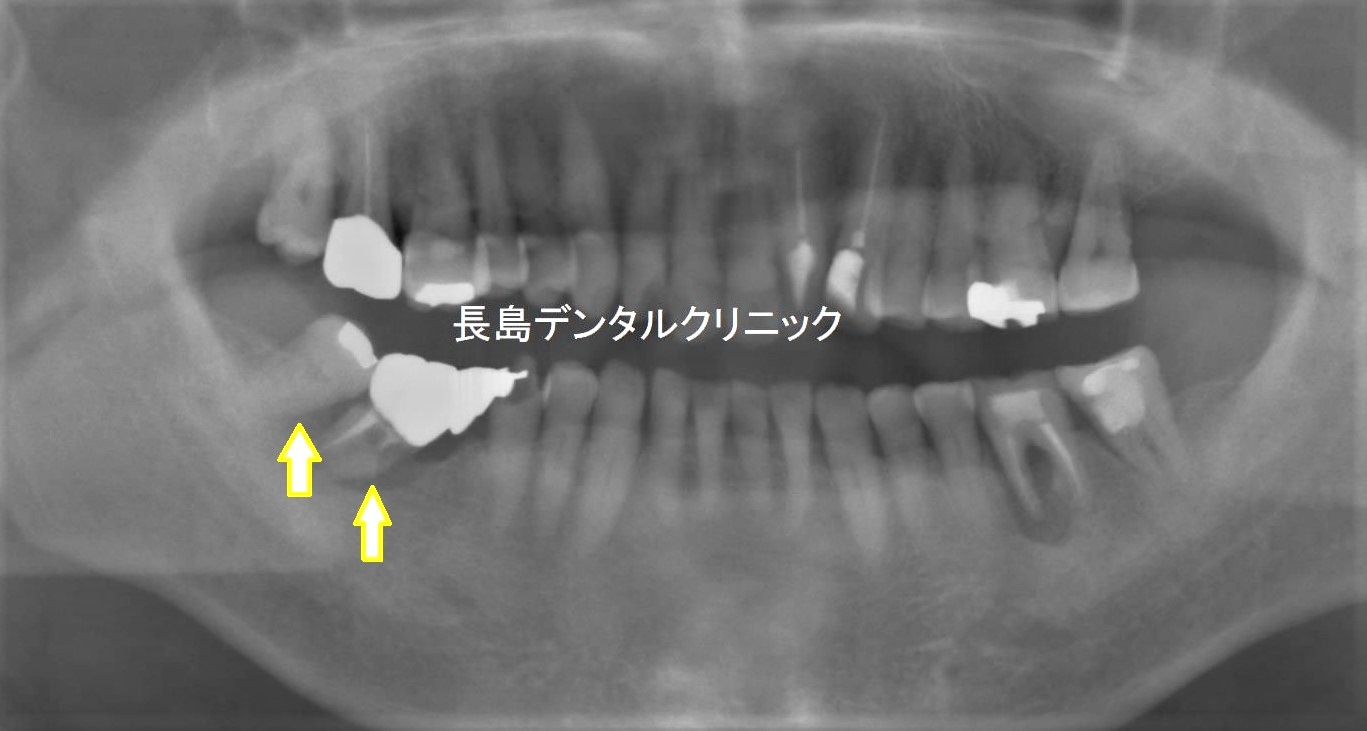

レントゲンを撮影すると

原因は歯周病によるもので

奥歯2本は抜歯です。

そのため顎の骨は十分厚みがありますので

抜歯即時埋入インプラント手術を

選択しました。